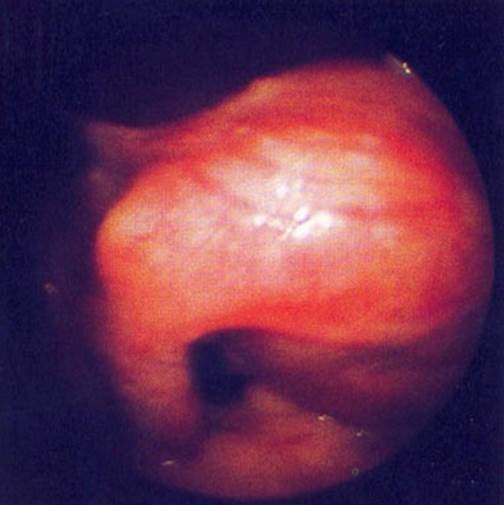

Больная В., 54 лет, поступила в больницу с жалобами на ноющую боль в левой подвздошной области, которая иррадиирует в левое бедро, учащенное, безболезненное мочеиспускание.

Данные лапароскопического исследования представлены на рисунке.

Ваш диагноз.

при лапароскопии:

+цистаденома яичника;//

субсерозная миома; //

внематочная беременность; //

рак яичника; //

нет правильного ответа